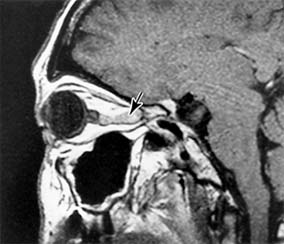

Intracranial meningiomas that may compress the optic nerve include those arising from the sphenoid wing, the tuberculum sellae (suprasellar meningioma), and the olfactory groove. Sphenoid wing meningiomas also produce proptosis, ocular motility disturbance, and trigeminal sensory loss (Figure 14-18). Surgical excision is generally effective in debulking intracranial meningiomas, but complete excision is often very difficult to achieve and recurrence rates are relatively high. Radiotherapy may be indicated as adjuvant or primary treatment. Pituitary adenoma and craniopharyngioma are discussed in the section on chiasmal disease (see below). The management of orbital causes of optic nerve compression is discussed in Chapter 13.

Figure 14-18

Figure 14-18: Axial MRI of sphenoid wing meningioma causing proptosis.